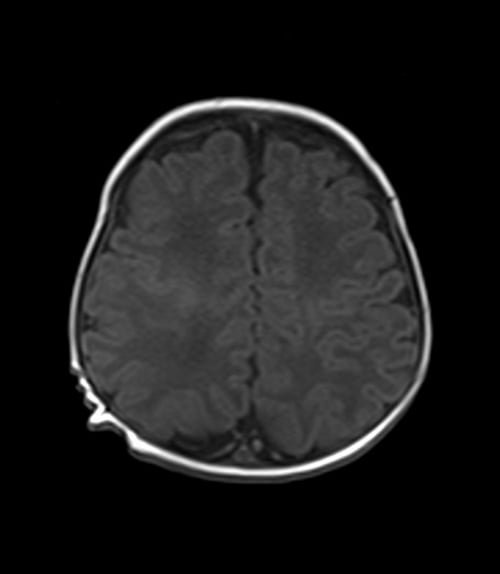

MRI pediatric brain axial T1 images